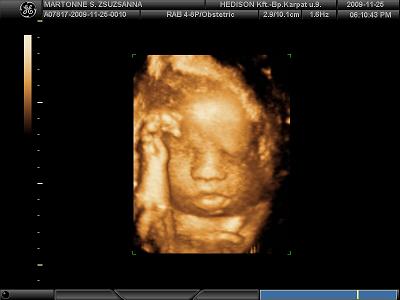

Köszönöm a képeket!!!!!

Tenci jól eltalálta, tényleg Jolie-s szája van Tominak!

És ha még Brad Pittre is fog hasonlítani............!!!!!!!!